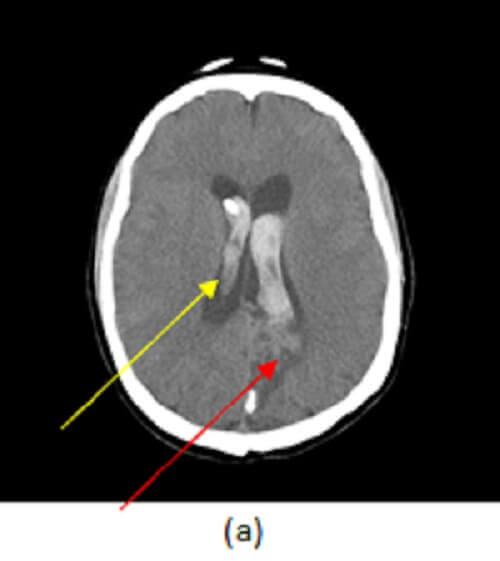

Figure 1: (a) axial image from a non contrast CT demonstrates intraparenchymal (yellow arrow) and intraventricular (red arrow) hemorrhage. (b, blue arrow), axial post contrast maximal intensity projection image from a CTA demonstrates a tangled vascular mass in the left parietal lobe consistent with an arteriovenous malformation (AVM). A saccular outpouching consistent with an intranidal aneurysm is also present adjacent to the ventricle (orange arrow). (c) Shaded surface display images show the AVM (green arrow) with early draining veins in to the deep (purple arrow) and superficial (white arrow) venous system. The intranidal aneurysm is also identified (brown arrow).